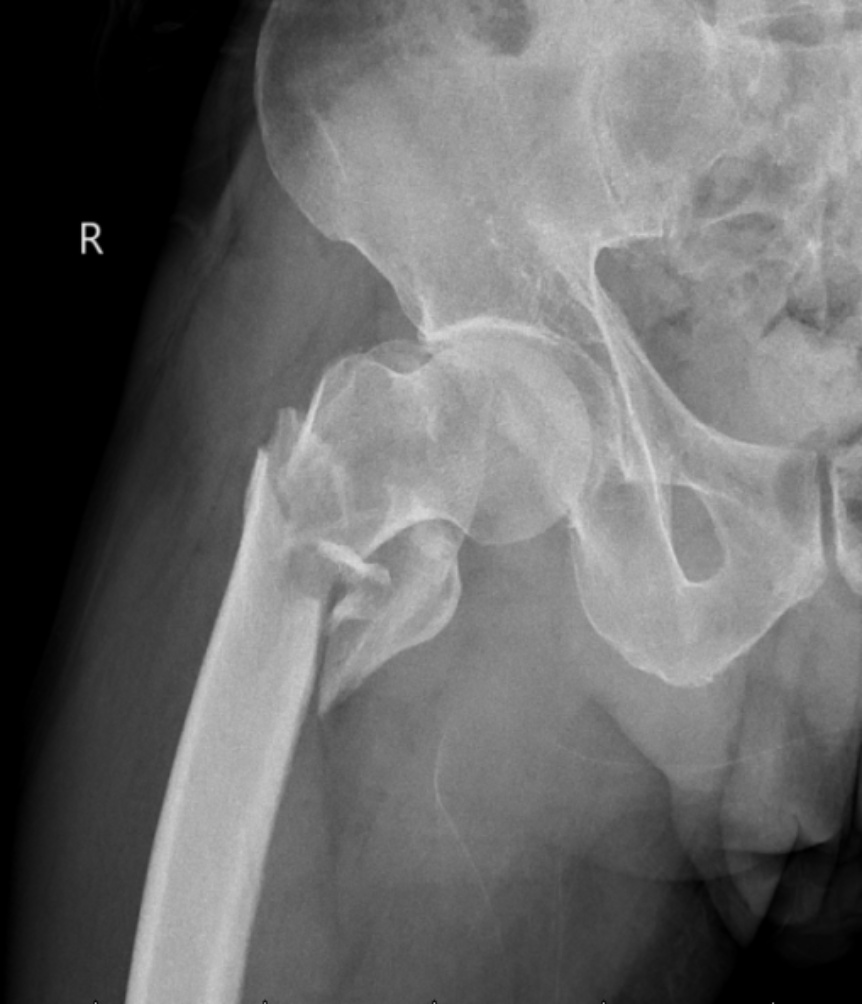

典型病例影像学表现见图1~10。图1为86岁女性右侧股骨转子间骨折(Evans Ⅲ型)患者,术前X线示骨折断端部分错位,术后X线示骨折位置可以及假体位置良好;图2显示了一名81岁男性患者,诊断为左侧股骨转子间骨折,类型为Evans V型,合并股骨干陈旧性骨折。患者接受了生物型加长柄半髋关节置换手术,并进行了股骨近端的钢丝捆扎内固定。术后X线示假体位置良好,股骨近端予钢丝捆扎固定;图3为87岁女性左侧股骨转子间骨折(Evans V型)患者,术后X线示假体位置良好,股骨大小转子骨折位置可,钢丝捆扎固定在位有效;图4为75岁女性左侧股骨转子间骨折(Evans V型)患者,术前X线示左侧股骨转子间骨折PFNA术后、骨折未愈合、内固定断裂。术后假体匹配良好,股骨近端钢丝内固定稳定可靠;图5为75岁男性左侧股骨转子间骨折(Evans IV型)患者,术后股骨大转子出现轻度位移,假体位置正常。图6为87岁男性左侧股骨转子间骨折(Evans V型)患者,给予DAA入路加长柄半髋关节置换,术前X线片,清晰地显示出左侧股骨转子间的骨折情况,术后X线影像,显示股骨的大小转子骨折位置良好,钢丝内固定装置在位稳定,假体位置良好;图7为77岁女性右侧股骨转子间骨折(Evans V型)患者,术前X线片显示右侧股骨转子间存在骨折且股骨大小转子均有累及和移位,术后X线片显示股骨小转子轻度移位,内固定装置位置稳定,假体位置良好;图8为70岁男性左侧股骨转子间骨折(Evans III型)患者,术前的X线片,清晰地显示了左侧股骨转子间的骨折情况,股骨近端髓腔钙化灶,术后假体位置满意;图9为77岁女性右侧股骨转子间骨折(Evans V型)患者,术前X线片,显示右侧股骨转子间及转子下部位骨折情况。术后假体匹配良好;图10为71岁男性右侧股骨颈骨折(Evans IV型)患者,术前X线片,显示右股骨转子间骨折的情况;术后X线表明股骨的大转子和小转子骨折位置保持良好,内固定装置稳固,术后假体位置正常。

Figure 2. An 81-year-old male patient with left intertrochanteric fracture of the femur (Evans type IV). (a) Before surgery; (b) After surgery

2. 81岁男性左侧股骨转子间骨折(Evans Ⅳ型)患者。(a) 术前;(b) 术后